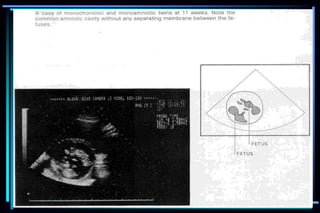

 Fetal number